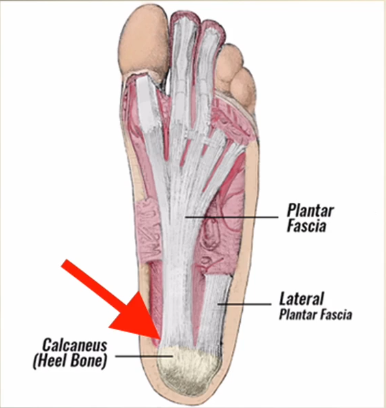

A fascite plantar é uma condição dolorosa que se localiza na região inferior do calcanhar, é uma patologia que ocorre como consequência de micro lesões repetitivas e inflamação crônica na fáscia plantar, principalmente na região de inserção no tubérculo medial do osso calcâneo.

A fáscia plantar é uma faixa grossa de tecido que fica na sola do pé. Ela começa no osso do calcanhar e vai até a base dos dedos, funcionando como uma espécie de “cinta elástica” que ajuda a sustentar o arco do pé. Sua função é dar estabilidade ao pé e absorver o impacto quando caminhamos, corremos ou ficamos em pé.

A fascite plantar se desenvolve quando a fáscia plantar é submetida à sobrecarga e, em consequência, sofre micro lesões que superam a capacidade do corpo de se curar.